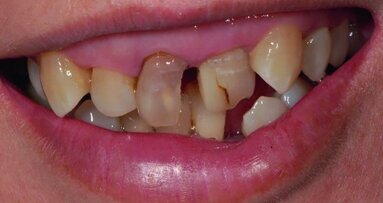

The patient, a woman in her early 60s, came to my office because she was having problems with a bridge (lower left) that had recently been replaced; she was unable to chew well. During the discussion she revealed that she was also having problems on the lower right, indicating that the problem was not local but one that involved the bite (Fig. 1).

On further examination, it was revealed that she not only had occlusal problems, but she also had moderate periodontitis throughout with bone loss especially impacting the lower anteriors. The patient had worn away her teeth and, as a result, suffered from severe malocclusion.

She had large diastemas between the upper and lower centrals with little occlusal guidance. Her temporal mandibular joints demonstrated hypermobility while opening and closing. The patient also had ill-fitting porcelain fused to metal crowns on teeth 3–5 and 31, 30, 12, 21 with metal exposure and a new zirconium bridge with flat occlusion on teeth 18–20. All prosthesis had poor colour matching and flat occlusion.

The periodontitis and bone loss were partially due to a traumatic bite that improperly distributed the occlusal forces laterally rather than perpendicularly so that the loading forces were forcing the lower anteriors to splay (Figs. 2–5).